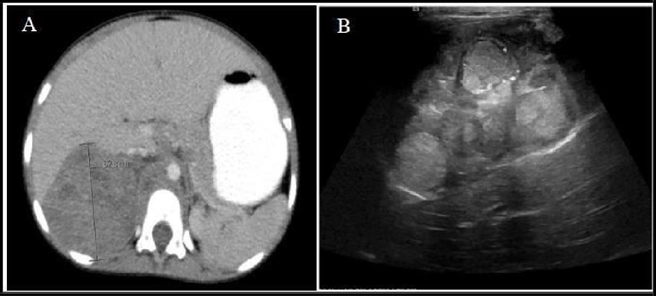

Solid pseudopapillary neoplasm of the pancreas: A report of two cases and review of the literature.